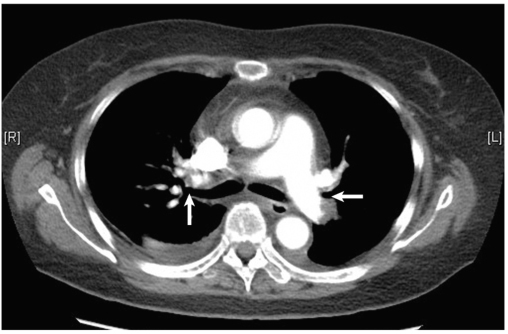

肺动脉CTA:右肺上叶动脉、中叶动脉、下叶动脉及其分支多发充盈缺损;左肺动脉主干末端、左肺上叶及下叶动脉及其分支多发充盈缺损(图1)。

图1肺动脉CTA显示双侧肺动脉多发充盈缺损(白箭)